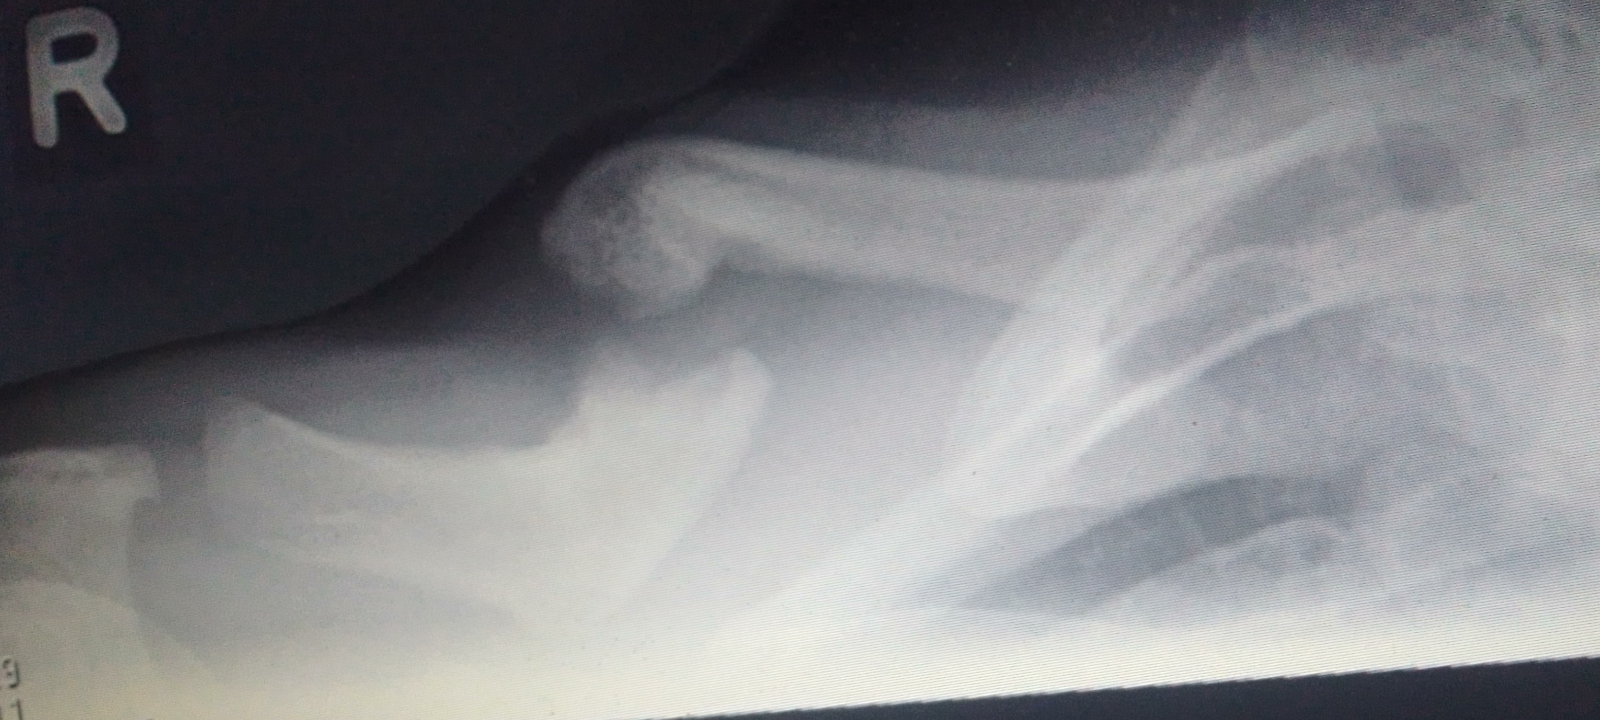

My right clavicle has been broken since birth.